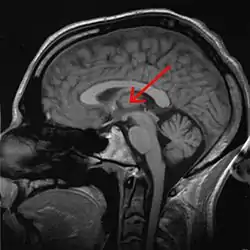

The thalamus (pl.: thalami; from Greek θάλαμος, "chamber")[1] is a large mass of gray matter on the lateral walls of the third ventricle forming the dorsal part of the diencephalon (a division of the forebrain). Nerve fibers project out of the thalamus to the cerebral cortex in all directions, known as the thalamocortical radiations, allowing hub-like exchanges of information. It has several functions, such as the relaying of sensory and motor signals to the cerebral cortex[2][3] and the regulation of consciousness, sleep, and alertness.[4]

Anatomically, it is a paramedian symmetrical structure of two halves (left and right), within the vertebrate brain, situated between the cerebral cortex and the midbrain. It forms during embryonic development as the main product of the diencephalon, as first recognized by the Swiss embryologist and anatomist Wilhelm His Sr. in 1893.[5]

The thalamus is a paired structure of gray matter about four centimetres long, located in the forebrain which is superior to the midbrain, near the center of the brain with nerve fibers projecting out to the cerebral cortex in all directions. The medial surface of the thalamus constitutes the upper part of the lateral wall of the third ventricle, and is connected to the corresponding surface of the opposite thalamus by a flattened gray band, the interthalamic adhesion. The lateral part of the thalamus is the phylogenetically newest part of the thalamus (neothalamus), and includes the lateral nuclei, the pulvinar and the medial and lateral geniculate nuclei.[6][7] There are areas of white matter in the thalamus including the stratum zonale that covers the dorsal surface and the external and internal medullary laminae. The external lamina covers the lateral surface and the internal lamina divides the nuclei into anterior, medial, and lateral groups.[8]